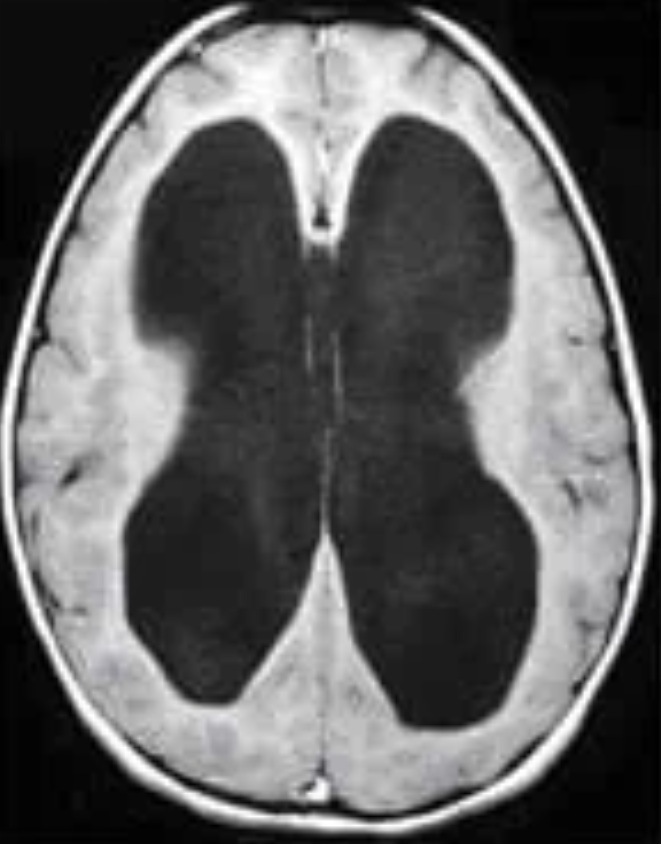

Estudio etiológico, manejo valvular y seguimiento clínico-radiológico a largo plazo.